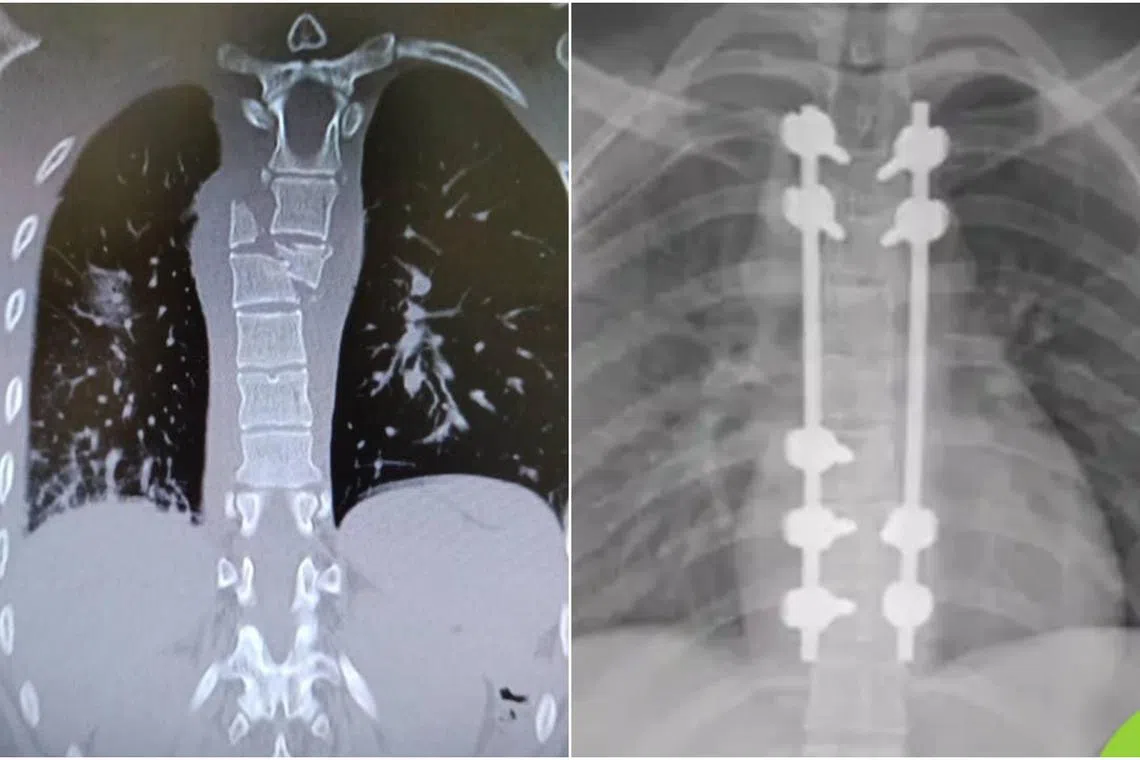

X-rays showing Ms Hong Mun Ying’s fractured spine (left) and her spine after surgery in Thailand (right).

PHOTOS: COURTESY OF HONG MUN YING

Ms Hong was one of those seriously injured, fracturing the fifth and sixth thoracic vertebrae in her spine. She also struck her head on the overhead luggage compartment and needed stitches on her scalp. The 23-year-old spent over 10 weeks recovering in Bangkok’s Samitivej Srinakarin Hospital and was one of the last few passengers on that flight to be discharged.

In Bangkok, corrective titanium plates were bolted onto her spine and doctors in Samitivej set her on a six-month course of recovery.